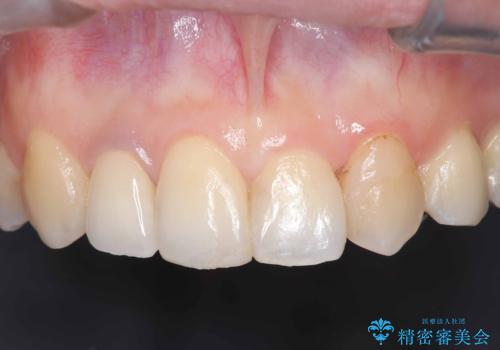

- 「前歯の見た目が気になる」を主訴に来院された患者様です。

失活歯による歯の変色とCR(コンポジットレジン)の劣化による審美不良でした。

オールセラミッククラウンで治療し見た目の改善を行いました。

まず劣化したCRと虫歯を除去した後、仮歯に置き換えました。歯のマージンラインを綺麗に削り光沢が出るまで研磨した後にオールセラミッククラウンの型取りを行っています。